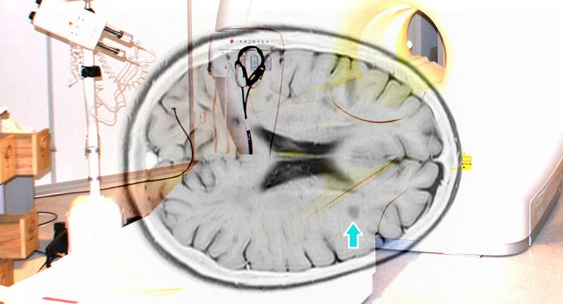

Пятилетний прием ублитуксимаба снизил число рецидивов рассеянного склероза

Прием препарата моноклональных антител против CD20-рецептора ублитуксимаба на протяжении пяти лет приводит к значительному клиническому эффекту у людей с рецидивирующим рассеянным склерозом.N + 1